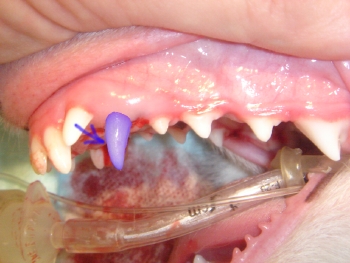

治療終了後の写真です。